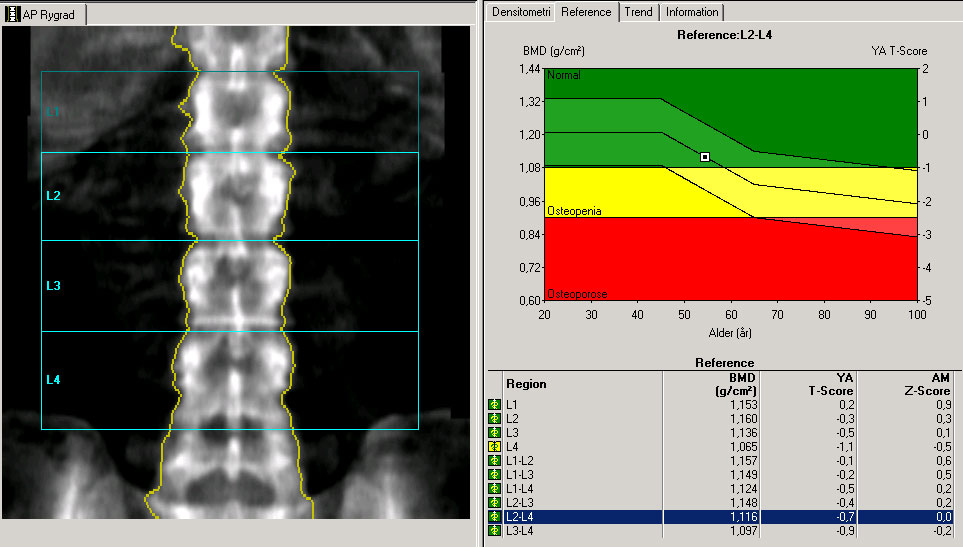

Rygsøjle, DXA-skanning, normalbillede

Skanningsbillede viser resultater fra en DXA-skanning af en normal rygsøjle, det vil sige uden knogleskørhed (osteoporose).

Til sammenligning billede af: Rygsøjle med knogleskørhed

Kilde til skanningsbillede: Afdeling for Nuklearmedicin, Herlev Hospital